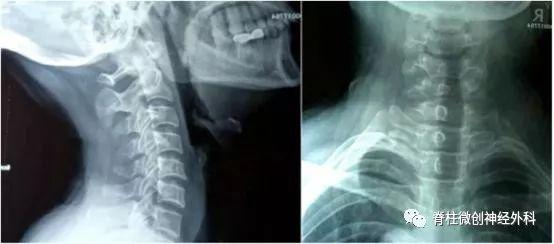

影像学资料:

从患者提供的颈椎侧位平片来看,并没有出现颈椎生理曲度变直或其他异常。但是,患者目前检查不完善,建议首先完善检查。

通常来说,颈椎侧位平片要在站立位,局部放松的时候拍摄。但是,这位患者不能明确拍的时候头部是处于后仰或是仰卧位。患者目前出现的颈肩部和手臂的疼痛可能是由于神经根的压迫。所以,建议患者首先完善检查,明确诊断。

❖1、完善检查:患者目前出现的肩膀和胳膊的疼痛症状可能是由于颈椎病变导致神经根孔出现骨性结构压迫,建议患者做颈椎双斜位明确是不是有神经根受压、神经根孔狭窄。